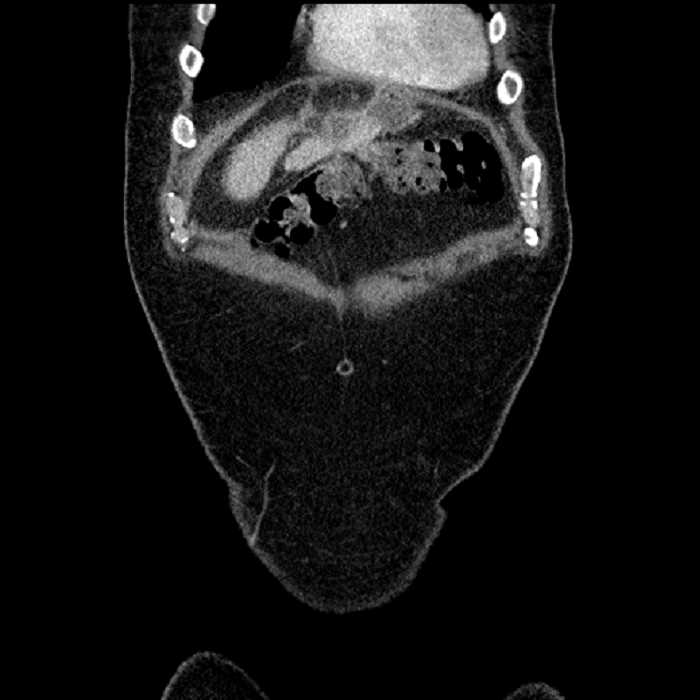

Age: 63

Sex: Male

Indication: Abdominal pain

• Large fluid density structure in hepatic segments 7 and 8 measuring 10 x 7 x 7 cm with internal septation and circumferential ill-defined low density compatible with edema

• Peripherally enhancing subcapsular collections along the anterior margin of the left hepatic lobe measuring 3 x 1 cm and 2 x 1 cm

• Clearly marginated fluid density structure in segment 7 and several other scattered tiny hypodensities, which likely represent cysts

• Mild mural thickening of a segment of the sigmoid colon with adjacent fat stranding and a 1.5 cm fluid and gas collection along the tip of an inflamed diverticulum

• Loss of the normal fat plane between this collection and adjacent loops of small bowel, which demonstrate mural thickening

• Hepatic abscess

Acute sigmoid diverticulitis complicated by a small contained perforation and a large abscess in the right hepatic lobe. Additional small subcapsular abscesses along the anterior margin of the left hepatic lobe.

Additionally, loss of the normal fat plane between the peridiverticular collection and adjacent thickened loops of small bowel raises the potential for an enterocolonic fistula.

• The classic CT imaging appearance is a double target sign with internal low density surrounded by an internal enhancing rim (capsule) and a low density external rim (edema)

Hepatic abscess showing the double target sign with low density internally surrounded by a thin inner enhancing rim (red arrow) and ill-defined outer low density rim (yellow arrow). Blue arrow indicates an internal septation. Red arrows: additional smaller subcapsular abscesses. Red arrow: focal contained perforation associated with diverticulitis.